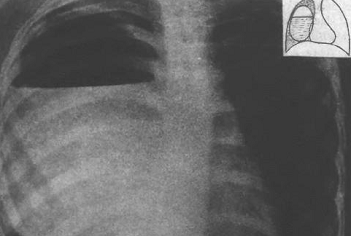

Рентгенограмма. Врожденная долевая эмфизема

верхней доли левого легкого у ребенка 1 месяца

Рис.

Легочный рисунок в верхней доле левого легкого

прослеживается плохо, органы средостения смещены вправо, купол диафрагмы

уплощён